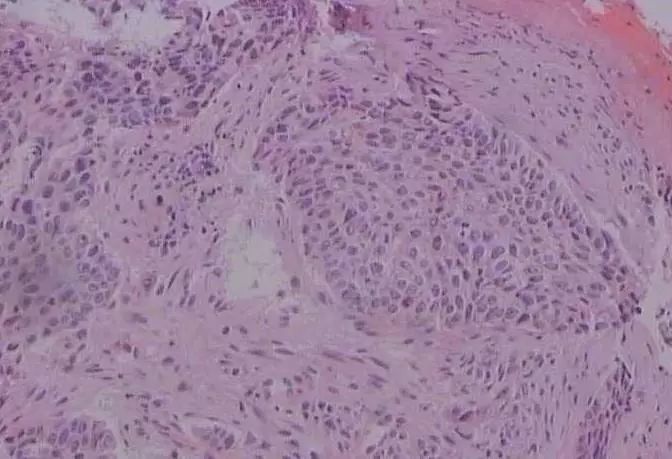

显微镜下的鳞状上皮细胞癌

大量增殖、广泛浸润